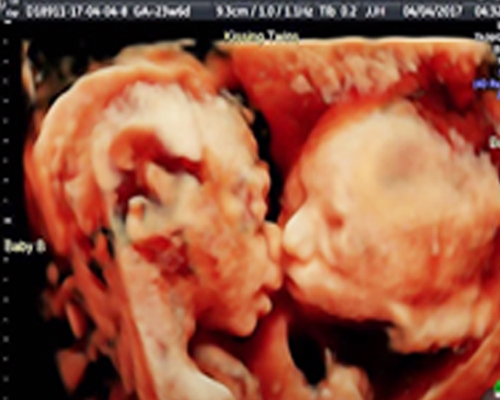

Hình ảnh chụp siêu âm cho thấy hai thai nhi sinh đôi của Carissa, đang mặt đối mặt nhau, trông như thể đang hôn nhau vậy. Nhìn thấy kết quả, cặp đôi thoáng sửng sốt trước khi vỡ òa trong sự ngạc nhiên lẫn hạnh phúc.

Bác sĩ thực hiện ca siêu âm John Hamburg chia sẻ: "Tôi đã thực hiện khoảng 15,000 ca siêu âm khác nhau, nhưng chưa bao giờ được thấy cảnh tượng hai thai nhi đối mặtt như đang hôn nhau thế này. Thường thì cặp sinh đôi một người nằm xuôi, và người kia sẽ nằm ngược."